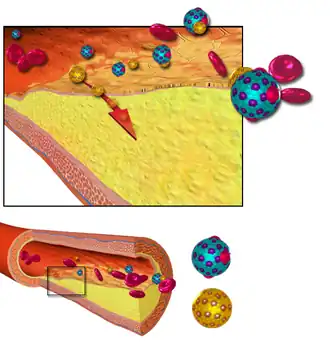

| Blood vessel-plaque and cholesterol | |

Arteriosclerosis, literally meaning "hardening of the arteries", is an umbrella term for a vascular disorder characterized by abnormal thickening, hardening, and loss of elasticity[3] of the walls of arteries.[4] This process gradually restricts the blood flow to one's organs and tissues and can lead to severe health risks brought on by atherosclerosis, which is a specific form of arteriosclerosis caused by the buildup of fatty plaques, cholesterol, and other substances in and on the arterial walls. Risk factors include family history, smoking, and obesity.

The lesions of arteriosclerosis begin as the intima (the innermost layer of a blood vessel wall) of an artery starts to fill up with the deposition of cellular wastes. As these start to mature, they can take different forms of arteriosclerosis. All are linked through common features such as the stiffening of arterial vessels, thickening of arterial walls and the degenerative nature of the disease.[6][7]

- Atherosclerosis is the narrowing of arteries from a buildup of plaque, usually made up of cholesterol, fatty substances, cellular waste products, calcium, and fibrin, inside the arteries. This affects large and medium-sized arteries; however, its positioning varies person to person.[9]